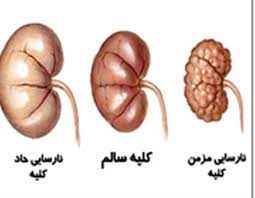

قیمت: 52٬000 تومان - دسته بندی فایل: پاورپوینتپاورپوینت نارسایی کلیه

فروش ویژه پاورپوینت حرفه ای نارسایی کلیه با تخفیف استثنایی فقط 62 هزار تومان تعداد اسلاید : 27 اسلاید